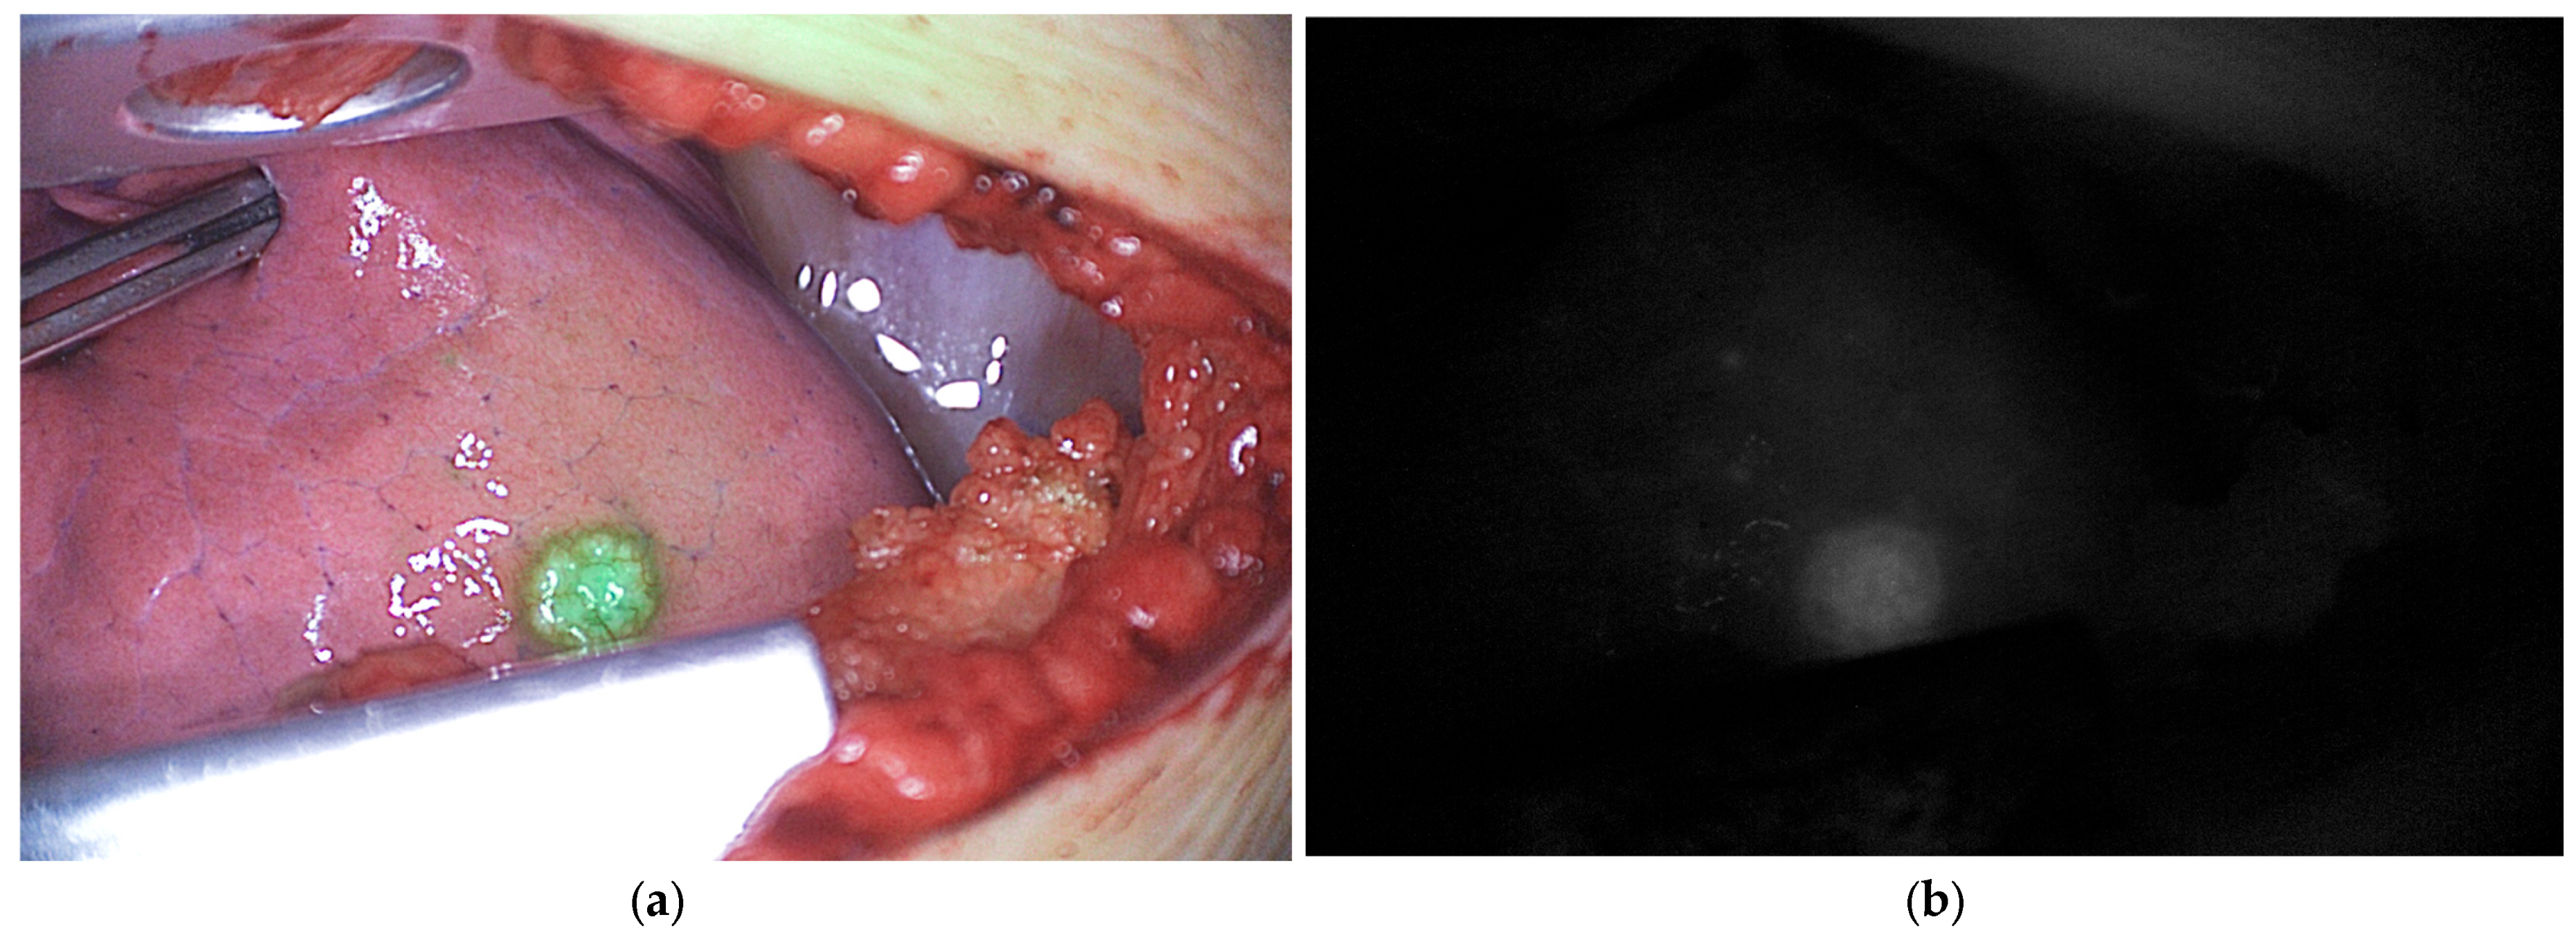

5.1.1. Hepatoblastoma

| Tumor imaging | Clinical | Pediatric | Hepatoblastoma | Identification of primary residual, and metastatic lesions | ICG 0.1–0.5 mg/kg, 24–96 h before surgery | [22,23,24,25,26,27,28,29,30,31,32,33] |